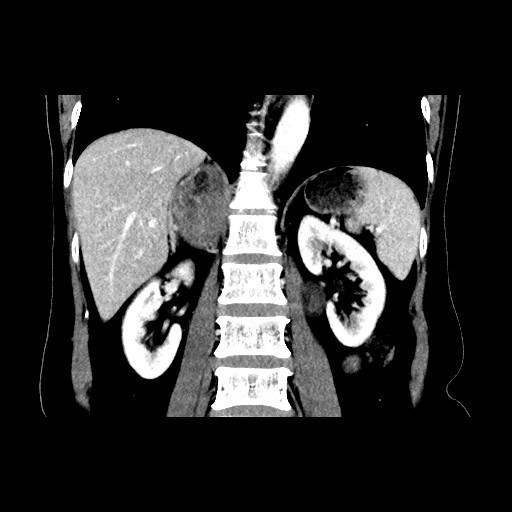

查体:血压:152/80mmHg。双肾区无红肿、隆起,双肾区叩击痛(-),双侧肋脊点、肋腰点压痛(-)。 辅查:CT平扫+增强扫描示:右侧膈下肾上腺区和左侧腰大肌病灶, 考虑为良性肿瘤,嗜铬细胞瘤可能性大,未除外其他

随访:病理回报示:嗜铬细胞瘤。 讨论:该例嗜铬细胞瘤具有较典型的影像表现,我们能看到右侧肾上腺椭圆形肿块,边界清楚,直径较大,这可区别于肾上腺腺瘤,后者一般小于2cm。增强扫描肿块明显强化,并可见无强化低密度区,可能是肿瘤常坏死或陈旧性出血引起。而且该患者有嗜铬细胞瘤引起的继发性高血压,不过追问病史没有典型的阵发性高血压发作。